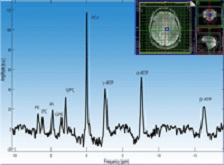

Rooney, Sammi: a 7T MR spectrum from the frontal white matter region of the brain (click to enlarge)

• Drs. RooneySammi, Cameron, and Bourdette: Magnetic resonance spectroscopy (MRS) techniques use the same basic hardware as MRI and can be used to non-invasively measure multiple aspects of tissue energetics. An overall goal of this project is to evaluate regional cerebral high-energy phosphate metabolism in people with MS. To accomplish this we apply 31P magnetic resonance spectroscopic imaging (MRSI) techniques using our 7T MR instrument. The 7T 31P MR spectrum at right was collected from the thalamic brain region of a healthy human subject (click the image to enlarge). The spectrum is part of a full-brain 3D MRSI acquisition that was collected in 35 minutes using a dedicated quadrature RF coil tuned to 120.3 MHz. The nominal voxel size of 8 cm3 (2 cm isotropic resolution; effective voxel size is larger) is indicated in two dimensions by the blue boxes on the scout water proton MR images at the top right. The signal to noise and spectral resolution were excellent in most brain regions of this volumetric acquisition. G(PE) refers to glycero(phosphoethanolamide), G(PC) is glycero(phosphocholine, Pi is inorganic phosphate, PCr is phosphocreatine, and ATP is adenosine triphosphate.